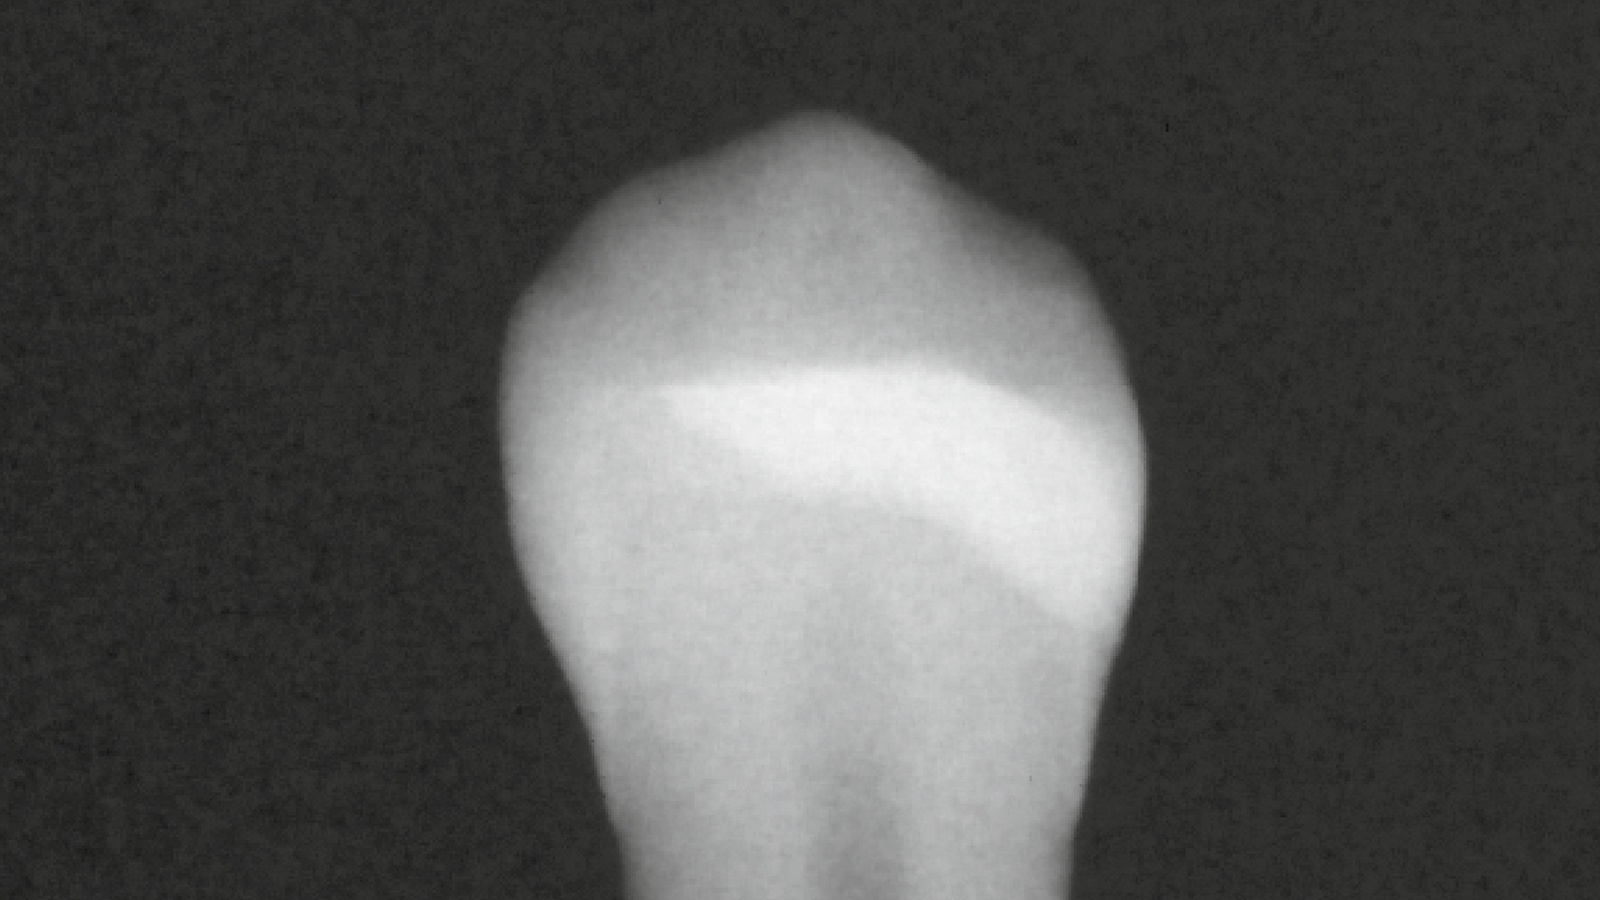

Its high radiopacity of more than 250%-AL allows for a safe and predictable diagnosis.

Is Charisma Bulk Flow ONE radiopaque?

Yes, Charisma Bulk Flow ONE fillings are easily recognized on X-rays which supports a reliable diagnosis. Its radiopacity with app. 300%-Al is much higher than the radiopacity of dentine (100%-Al) and enamel (200%-Al).